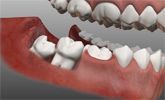

Зубы мудрости – лечить или удалять?

Зубы мудрости. Почему нужно удалять?

Один из самых часто задаваемых пациентами вопросов - почему нужно удалять зуб мудрости (или третий моляр)

Зачем нужны зубы мудрости?

Зубы мудрости, известные также как «восьмерки» или «третьи моляры», прорезываются, как правило, в возрасте от 16 до 25 лет

Зубы мудрости: за и против

Многие сталкиваются с проблемами, когда у них начинают прорастать зубы мудрости.

Как удаляют зуб мудрости

Зубы мудрости (они же третьи моляры или «восьмерки»), как правило, прорезываются в возрасте около 20-25 лет.